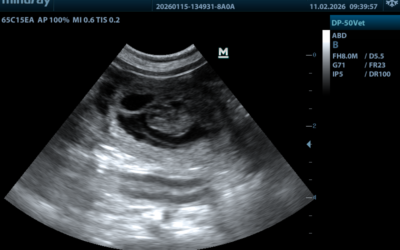

Arztbesuch am Schmittwoch

Unser Tierarzt hat noch kurz vor dem grossen Start der fünften Jahreszeit sein Ultraschallgerät angeworfen. Juhui wir haben was gesehen.